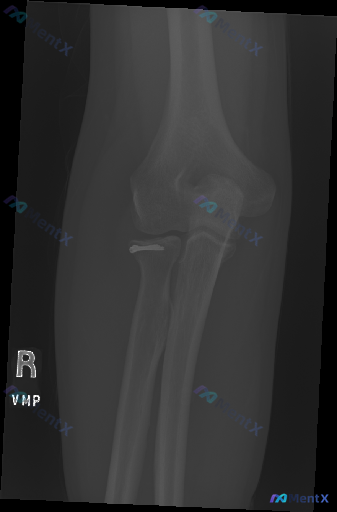

整理到一张右侧肘关节正位X光片的分析资料,先放核心影像所见: - 投照为右肘正位,尺骨鹰嘴窝部分重叠略有旋转; - 肱骨远端、尺骨近端骨质连续,关节对位良好; - **重点发现:桡骨头处可见明显金属内固定物(钉帽)影,桡骨头颈部有陈旧性骨折手术复位内固定征象,固定位置较好,未见明显松动移位,骨皮质修...